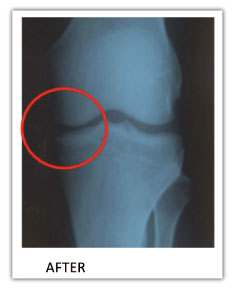

But now look at the “AFTER” image.

See how much farther apart the bones are… with a clear, dark space in between?

As incredible as it is… the X-ray clearly shows…